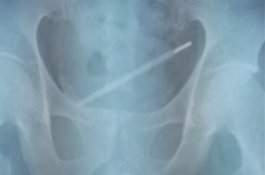

Pria ini Masukkan Termometer ke P*nis, Terjebak di Kandung Kemih 11 Hari

News

- 21 September 2019 17:02